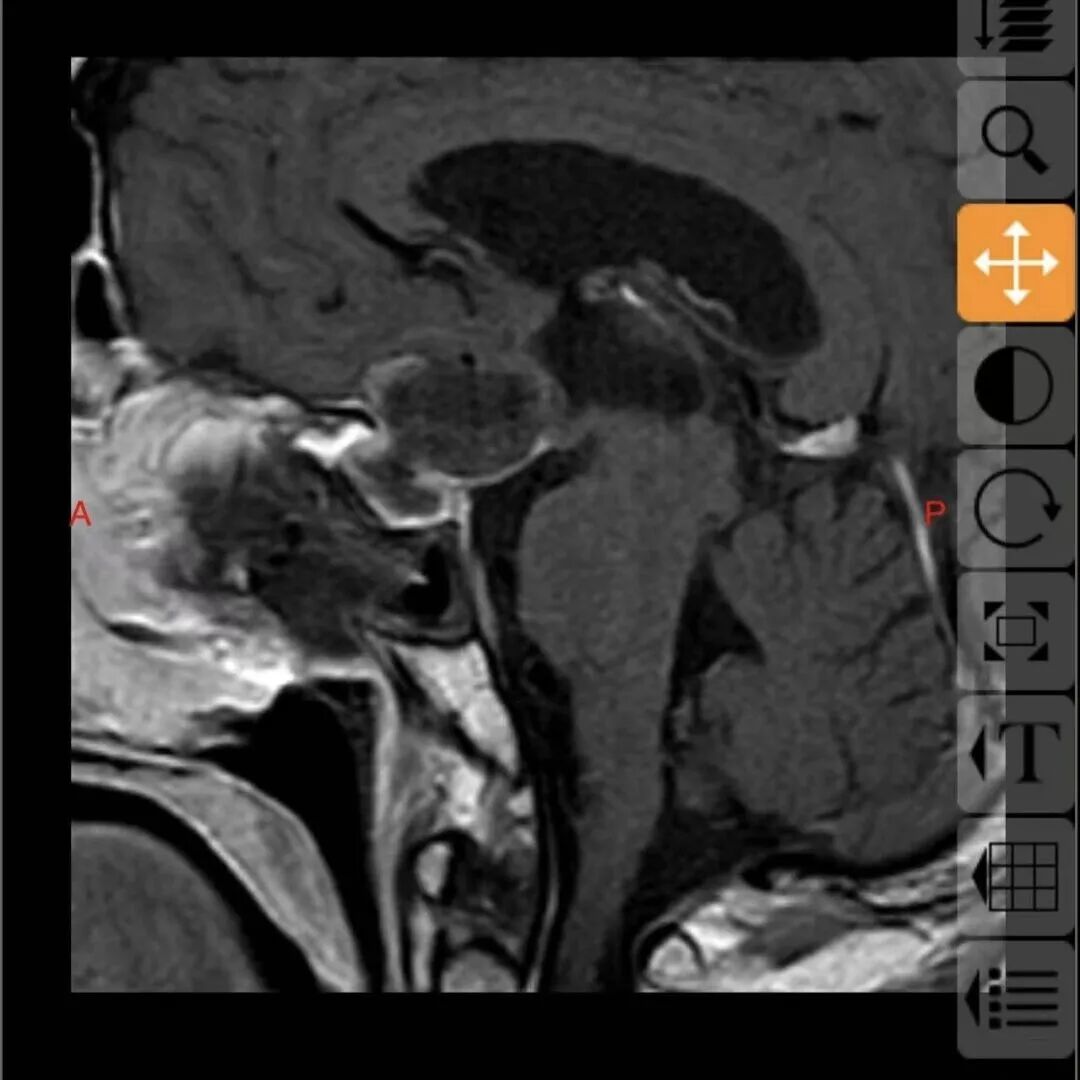

68岁的邓大叔是一位饱受垂体瘤困扰的“老战士”,11年前他经鼻行垂体瘤手术,几年后垂体瘤复发再次通过伽马刀治疗,经过两次历练后的他以为之后就可以高枕无忧,没想到近期的复查报告显示肿瘤“卷土重来”,且这次情况远比之前“棘手”,复发的肿瘤不仅从鞍内生长到鞍上,还与大脑的“生命线”——前交通动脉以及掌管意识记忆的三脑室底粘连紧密,甚至朝一侧颈内动脉上方生长,就像一颗埋在大脑深处的“不定时炸弹”,位置险要,结构复杂。

这颗复杂的“炸弹”究竟该如何拆除?张治国主任仔细研究了邓大叔的病情后,提出了一个大胆的方案:再次施行经鼻蝶微创手术。

最终,由张治国主任主刀,为邓大叔顺利实施了这例高难度的经鼻蝶微创手术,肿瘤被完整、精准地切除,紧密粘连的前交通动脉及三脑室底均保护完好。